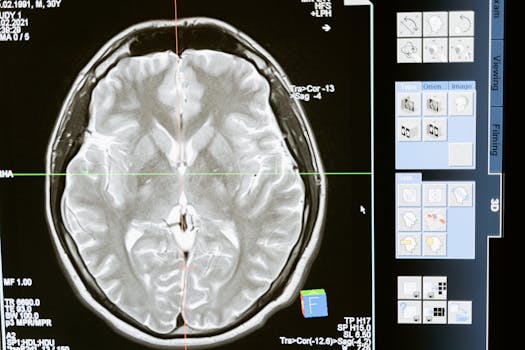

今回は発達障害(脳機能障害)についての記事です。

①発達障害とは脳の神経伝達物質による特性であり、度合いによっては通院や投薬など、周囲のサポートが必要なものです。

発達障害(脳機能障害)とは、神経発達に影響を及ぼし、さまざまな特性や行動に影響を与えます。また周囲の理解がない場合、鬱などの2次障害につながる場合があります。/